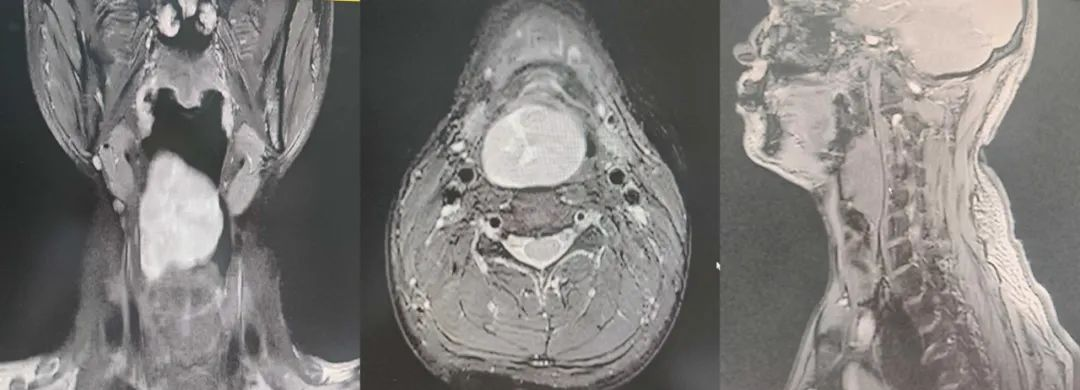

日前,39岁的杨先生近2年自觉讲话时如同口中含物,于1个月前体检时发现咽喉部巨大肿物,于是至我院就诊。耳鼻咽喉头颈外科主任王晓茜接诊后,给予患者纤维喉镜检查提示喉咽后壁巨大肿物,表面光滑,遮挡声门,建议住院手术治疗,入院后完善咽喉增强磁共振提示喉部巨大肿块,考虑神经鞘瘤或混合瘤可能。

▲术前增强核磁图像

经王晓茜主任、徐春来主任医师及团队成员王卫雄、陈思洁医生认真进行病例讨论,制定了周密手术方案。徐春来主任医师为患者行局部麻醉下气管切开及全身麻醉下行内镜辅助喉部肿物等离子切除术,手术顺利完成。术中于0°内镜下可见喉咽后壁偏右侧巨大表面光滑新生物,肿物黏膜表面血管丰富,术中切开黏膜、黏膜下组织、肌肉层可见表面淡黄色肿物膨出,沿肿物周边剥离,肿物大小约为5.0cm×5.0cm×2.5cm,12天后拔出气管套管,气管造口对位缝合,患者治愈出院。术后随访至今粘膜愈合良好,无复发。术后病理结合免疫组化诊断意见:丛状神经鞘瘤。